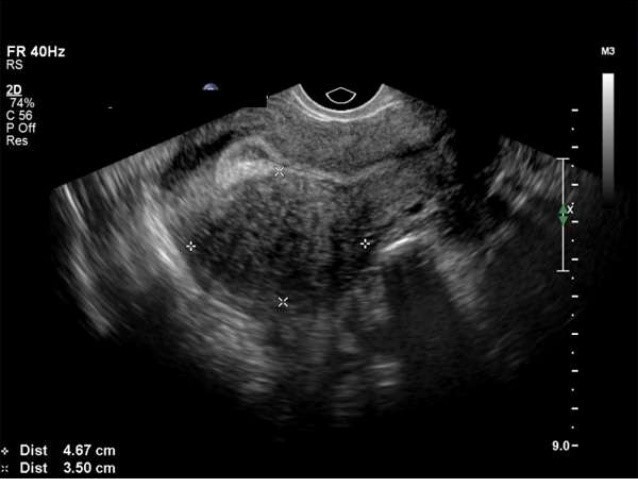

Principale complication de la stimulation ovarienne multifolliculaire

Examen de première intention

Le syndrome d’hyperstimulation ovarienne (HSO) est une complication iatrogène de la stimulation ovarienne supraphysiologique. Le syndrome est presque exclusivement associé à la simulation exogène aux gonadotrophines. Le HSO grave est dû à la libération de peptides vasoactifs par les cellules de la granulosa au sein des ovaires hyperstimulés.

C’est l’hCG qui est responsable de « l’emballement » des ovaires.

Le risque principal est l’hémoconcentration, avec pour conséquence le risque thromboembolique veineux.

Votre échographie retrouve des ovaires mesurés à 14 et 13 cm, ainsi qu’un épanchement important du cul-de-sac de Douglas.